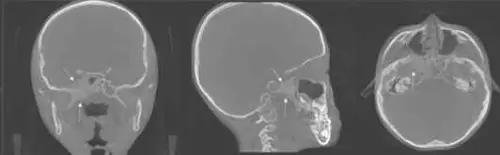

또한 턱관절의 경조직 평가에 유용한 CBCT를 통해 턱관절의 가장 흔한 질환 형태인 턱관절의 퇴행성골관절염의 진단이 가능했다. 퇴행성 골관절염은 초기에는 관절부의 연조직 구성 요소가 파괴되고 이어서 골의 흡수와 증식이 나타나는 위험한 비염증성 질환이다.

「사진 설명」턱관절 퇴행성골관절염으로 진단